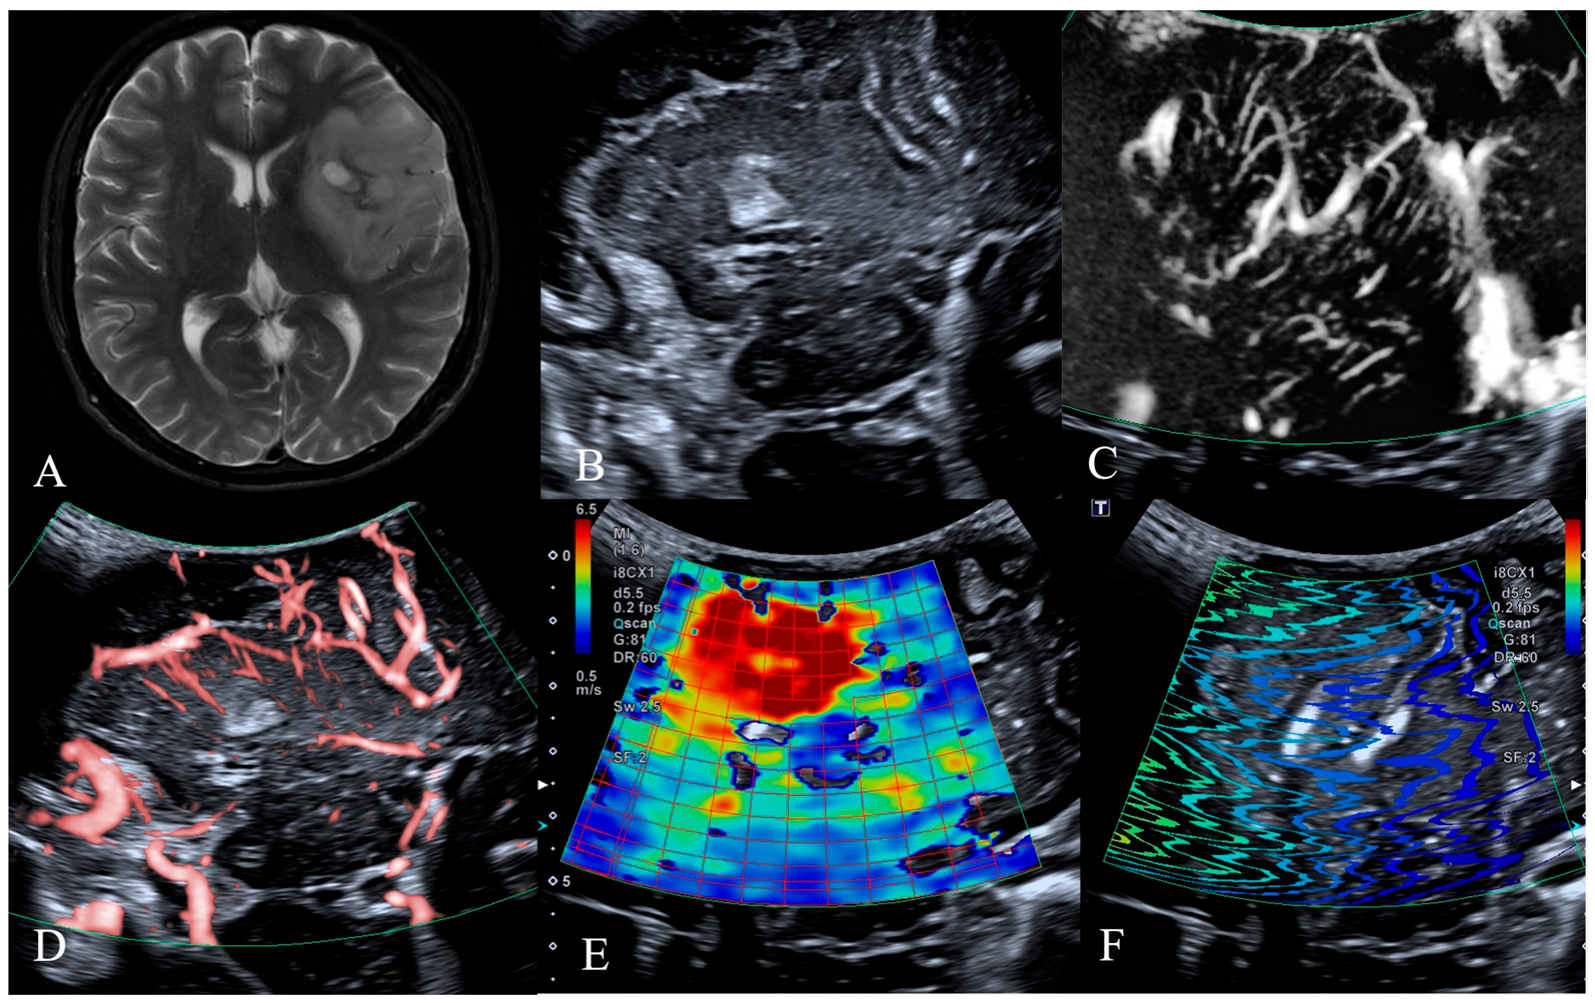

| HGG (n, %) | LGG (n, %) | p Value | |

|---|---|---|---|

| Tumor Vessels | 0.001 * | ||

| Dilated and bent vessels | 18 (37.5%) | 2 (4.2%) | |

| Straight and branching vessels | 7 (14.6%) | 13 (27.1%) | |

| Avascular | 5 (10.4%) | 3 (6.3%) | |

| Vessels Around the Tumor | 0.001 * | ||

| Distorted and surrounding vessels | 20 (41.7%) | 2 (4.2%) | |

| Straight and penetrating vessels | 6 (12.5%) | 9 (18.8%) | |

| Normal cerebral vessels | 4 (8.3%) | 7 (14.6%) | |

| Total | 30 (62.5%) | 18 (37.5%) |

| Tumor Vessels | 0.002 * | ||

| Dilated and bent vessels | 3 (6.3%) | 17 (35.4%) | |

| Straight and branching vessels | 13 (27.1%) | 7 (14.6%) | |

| Avascular | 6 (12.5%) | 2 (4.2%) | |

| Distorted and surrounding vessels | 4 (8.3%) | 18 (37.5%) | |

| Straight and penetrating vessels | 12 (25.0%) | 3 (6.3%) | |

| Normal cerebral vessels | 6 (12.5%) | 5 (10.4%) | |

| Intratumoral Young’s modulus | 17.8 ± 10.3 | 15.1 ± 16.6 | 0.514 |